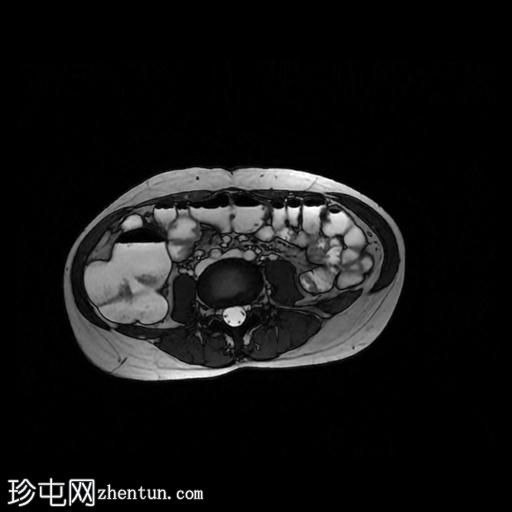

轴位T1加权像

增强脂肪抑制

回肠末端及盆腔回肠肠袢可见长段肠壁增厚及强化,肠周血管丰富,呈“梳状征”,并可见明显的纤维脂肪浸润。

未见瘘管、积液、腹水或梗阻。

磁共振肠道造影(MRE)结果支持克罗恩病的诊断,显示远端及末端回肠以活动

性病

变为主,并可见明显的肠周血管。